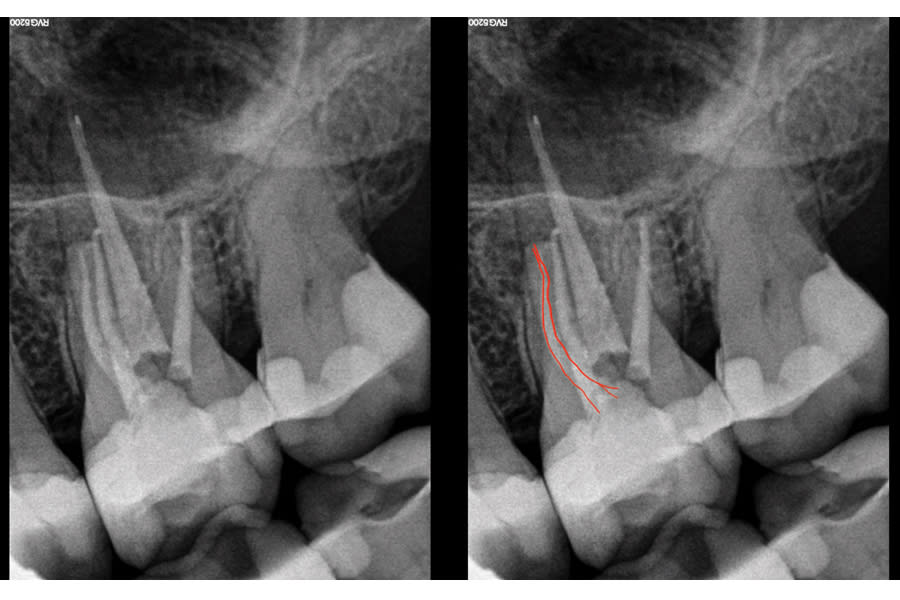

This case illustrates the value of contemporary reciprocating systems in addressing anatomical variations that can compromise primary endodontic success. A 62-year-old female patient was referred to the author’s practice due to persistent discomfort during mastication localized to the maxillary left first molar. Clinical examination revealed mild percussion sensitivity. A CBCT scan confirmed a previously untreated second mesiobuccal (MB2) canal and a periapical lesion associated with the mesiobuccal root. Thus, nonsurgical orthograde retreatment was chosen. Because the intricate morphology of MB2 canals can prove challenging for traditional rotary NiTi systems, the author has adopted the use of reciprocating single-file techniques, which offer enhanced safety. In this case, the author used the EdgeOne R Utopia™ R20 (EdgeEndo, edgeendo.com), a single-file reciprocating instrument designed for tight, calcified, and/or highly curved canals. Its S-shaped cross-section ensures cutting efficacy and fatigue resistance, while a proprietary heat treatment enhances both torsional strength and flexibility. The case was completed using standard irrigation protocols, followed by single-cone obturation with EdgeOne R Utopia™ gutta-percha points (EdgeEndo) and EdgeBioceramic™ Sealer (EdgeEndo) for a biocompatible and hermetic seal. Postoperative radiographs confirmed a well-centered fill and adequate canal debridement. The patient reported no significant postoperative discomfort and was asymptomatic within days.

EdgeOne R Utopia R20 successfully negotiated a narrow, double-curved MB2 canal without the need for glide path preparation or multi-instrument techniques. The reciprocating motion reduces continuous torsional stress, improves resistance to cyclic fatigue, and preserves canal anatomy.

R20’s proprietary heat treatment improves torsional resistance and flexibility, enabling safer navigation in highly curved or calcified canals. The R20 maintained working length and canal integrity, minimizing risk of ledging, transportation, or instrument separation.